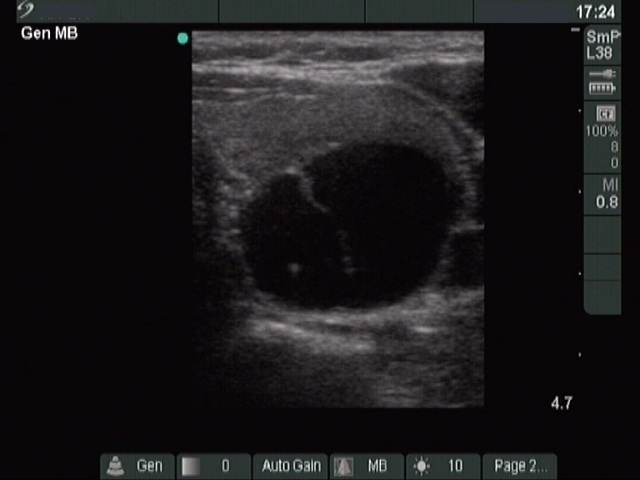

Clinical presentation: a 40-year-old woman was sent for ethanol sclerotherapy. Her thyroid cyst was evacuated three times but after each occasion the cyst got refilled within a week. FNAC resulted in a benign cystic lesion.

First row: before the first session of sclerotherapy. There was a cystic nodule in the left lobe with the dimensions of 32x27x42 mm (width x depth x length). 5 sessions of ethanol sclerotherapy was administered.